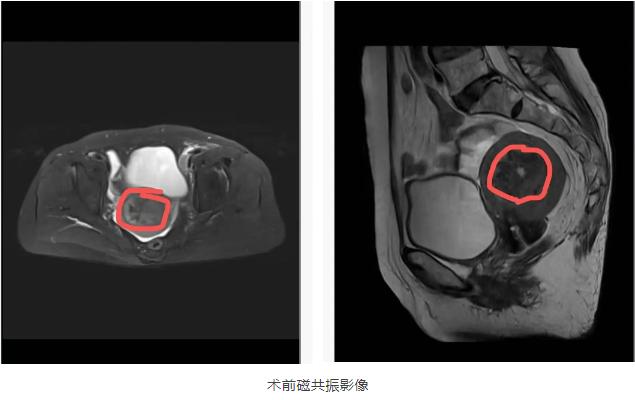

74岁的曹奶奶,绝经已有20余年,近日突然出现不规则阴道出血。在医院门诊彩超及诊刮病理提示“(子宫腔)腺癌和低分化癌(低分化腺癌可能性大)”。

妇产科李昉主任医师团队联合麻醉科等科室开展多学科会诊,反复研读患者的各项检查报告,全面评估她的身体耐受度、肿瘤分期等关键信息,最终制定了“腹腔镜下筋膜外全子宫切除 + 双侧输卵管卵巢切除 + 前哨淋巴结切除术”的精准手术方案。手术当天,李昉主任率郭靳静副主任医师,凭借精湛的腹腔镜操作技巧,在狭小的术野中精准分离组织,包绕血管的4个大淋巴结也在腹腔镜下完美的剥出!